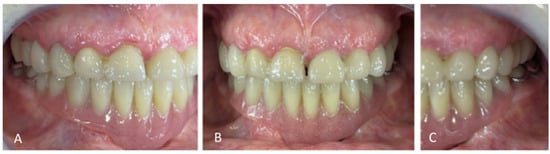

Figure 7.

Occluded arches views after treatment: (A) right view, (B) front view, (C) left view.

For the mandibular metal-framed removable partial denture, a digital impression was made using the 3Shape intraoral scanner. After the framework try-in, maxillomandibular relationship records were obtained using Aluwax (Aluwax Dental Products Co., Allendale, MI, USA), to accurately mount the casts on the articulator. The set-up was evaluated before polymerization. Upon prosthesis insertion, the occlusion was verified to ensure group function. Figure 1B, Figure 7 and Figure 8 illustrate the final treatment outcome.